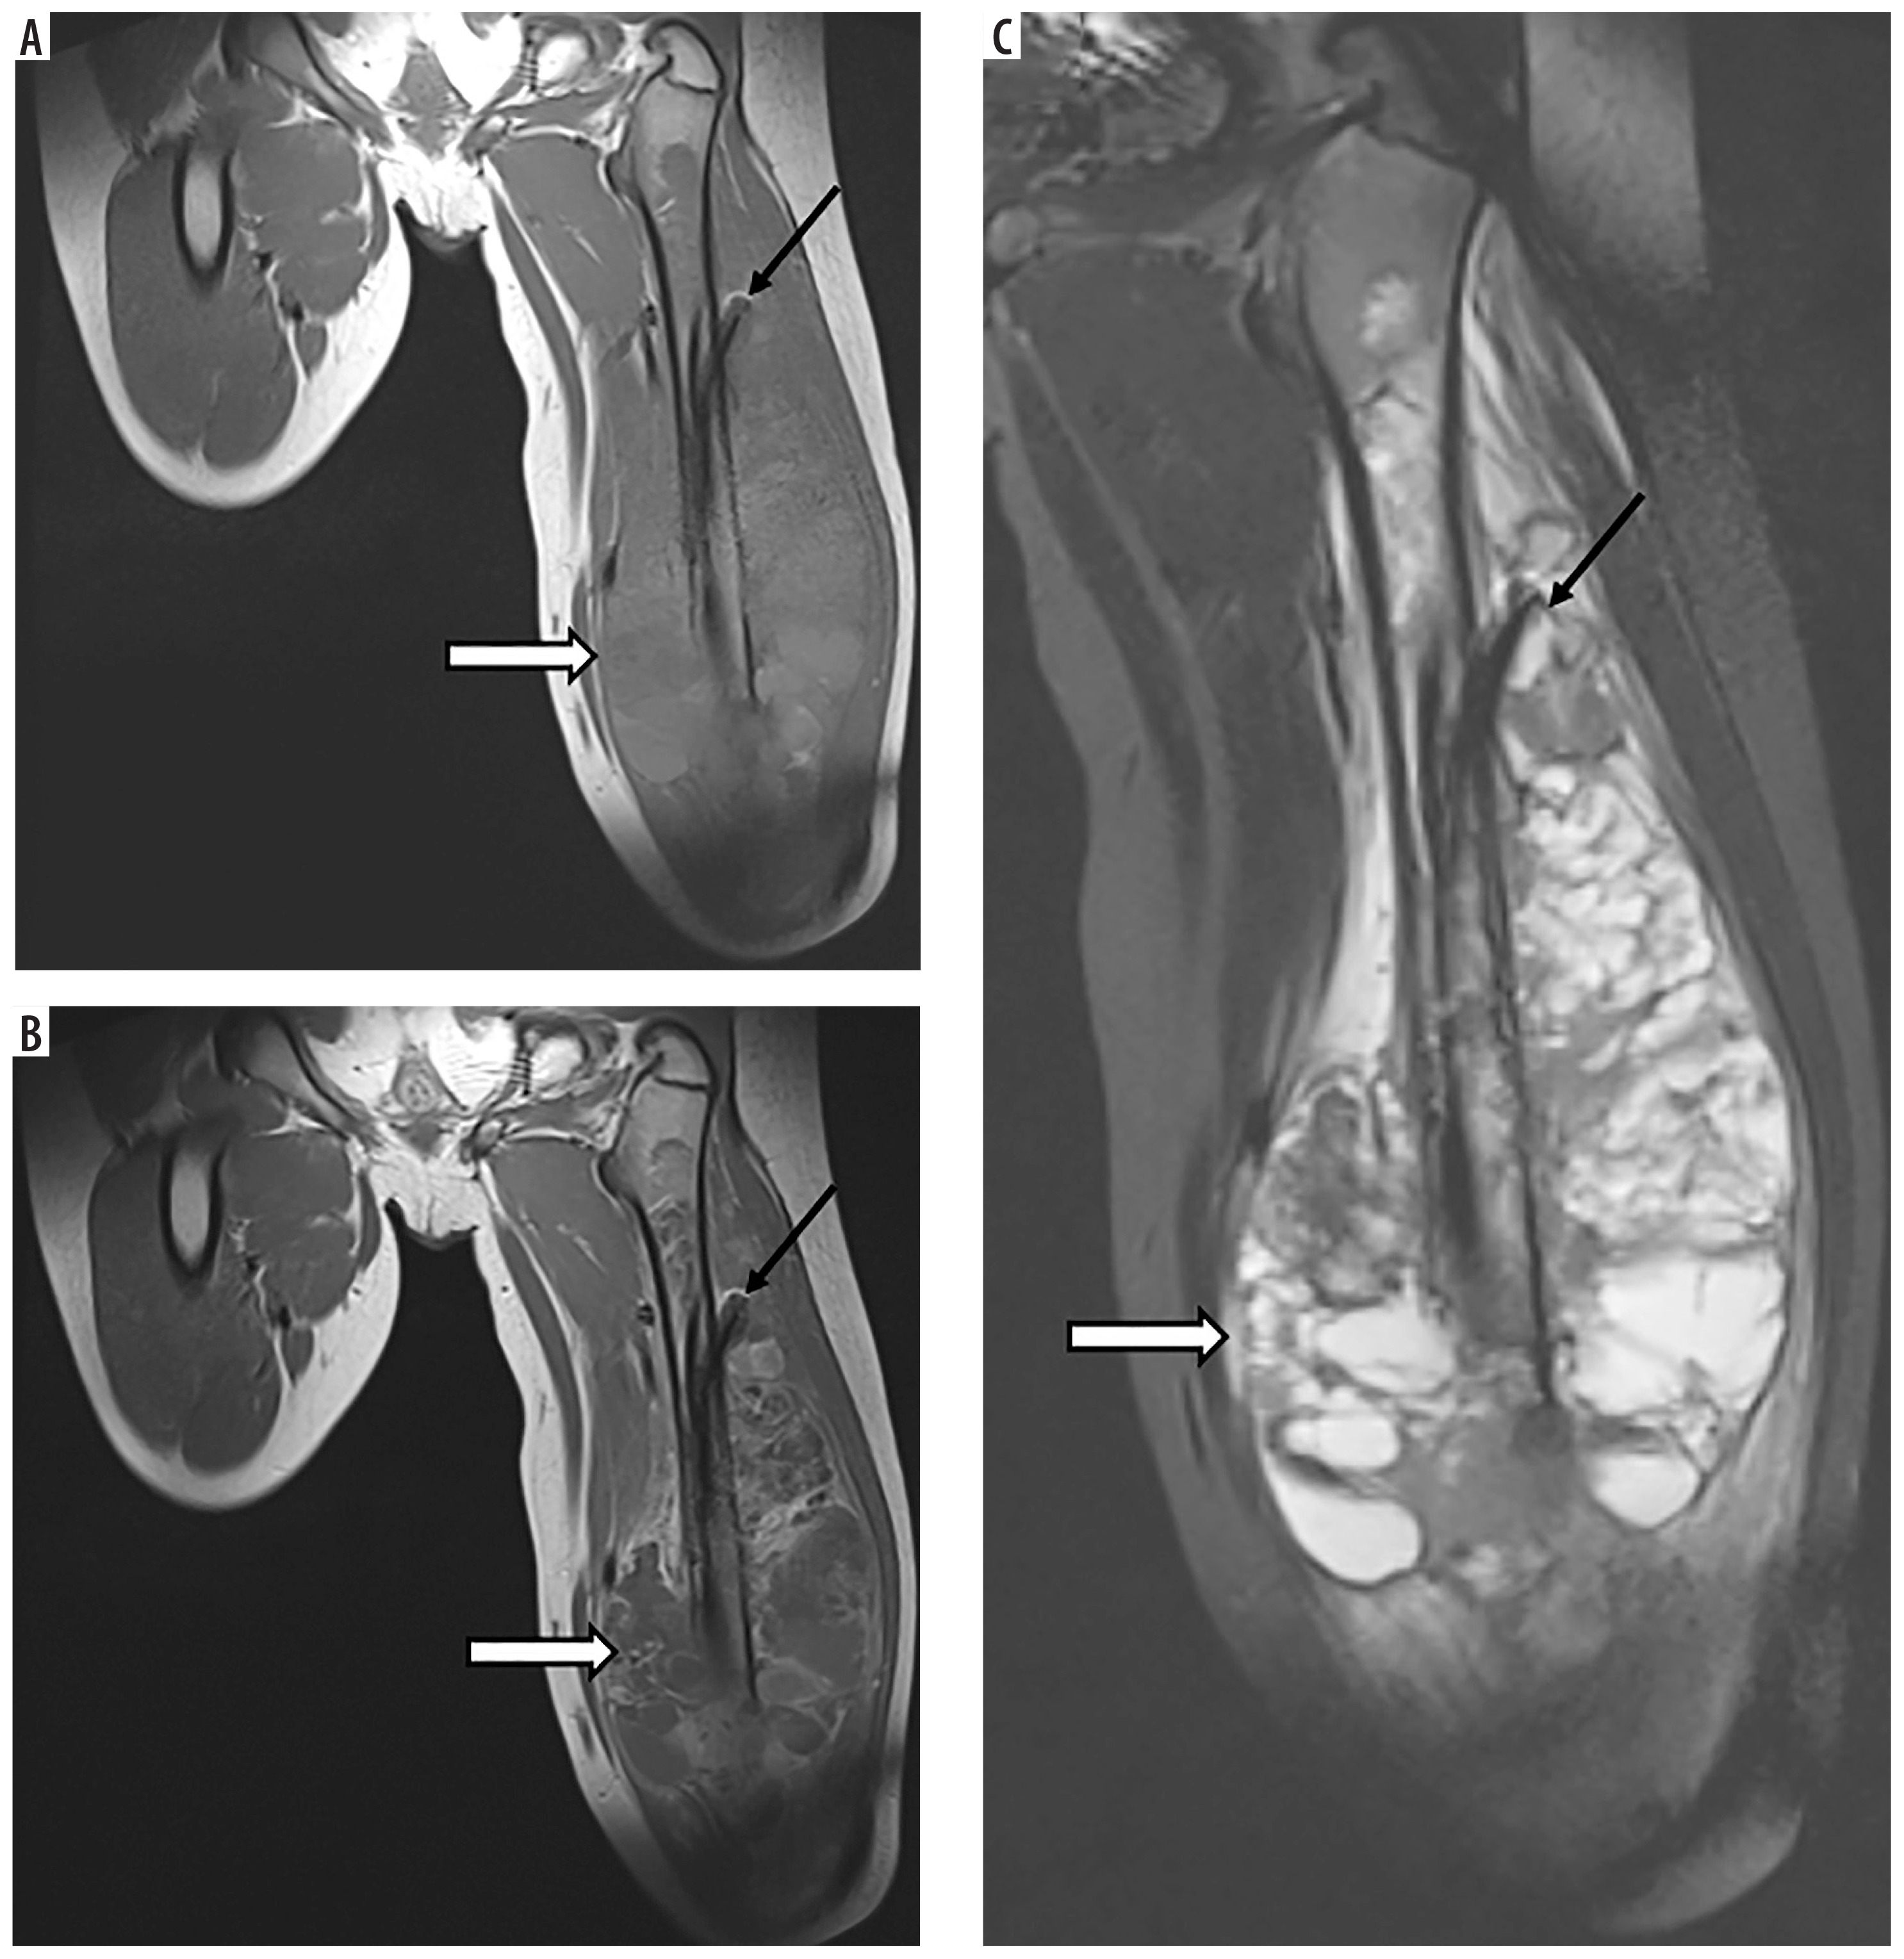

Figure 3

A 7-year-old patient (No. 50) with Ewing sarcoma of the right fibula (asterisks): A) T2-weighted sagittal image, B) T1-weighted sagittal image with contrast enhancement. Follow-up study after 6 months, after surgery and radiotherapy, no lesions (thick black arrow): C) coronal T1-weighted image. Pleomorphic sarcoma of the right tibia 3.9 years later (thin white arrows): D) coronal T1-weighted image, E) T2-weighted image with fat saturation, F) axial DWI, G) corresponding ADC map, confirming diffusion restriction, axial T1-weighted images before (H) and after (I) contrast medium administration